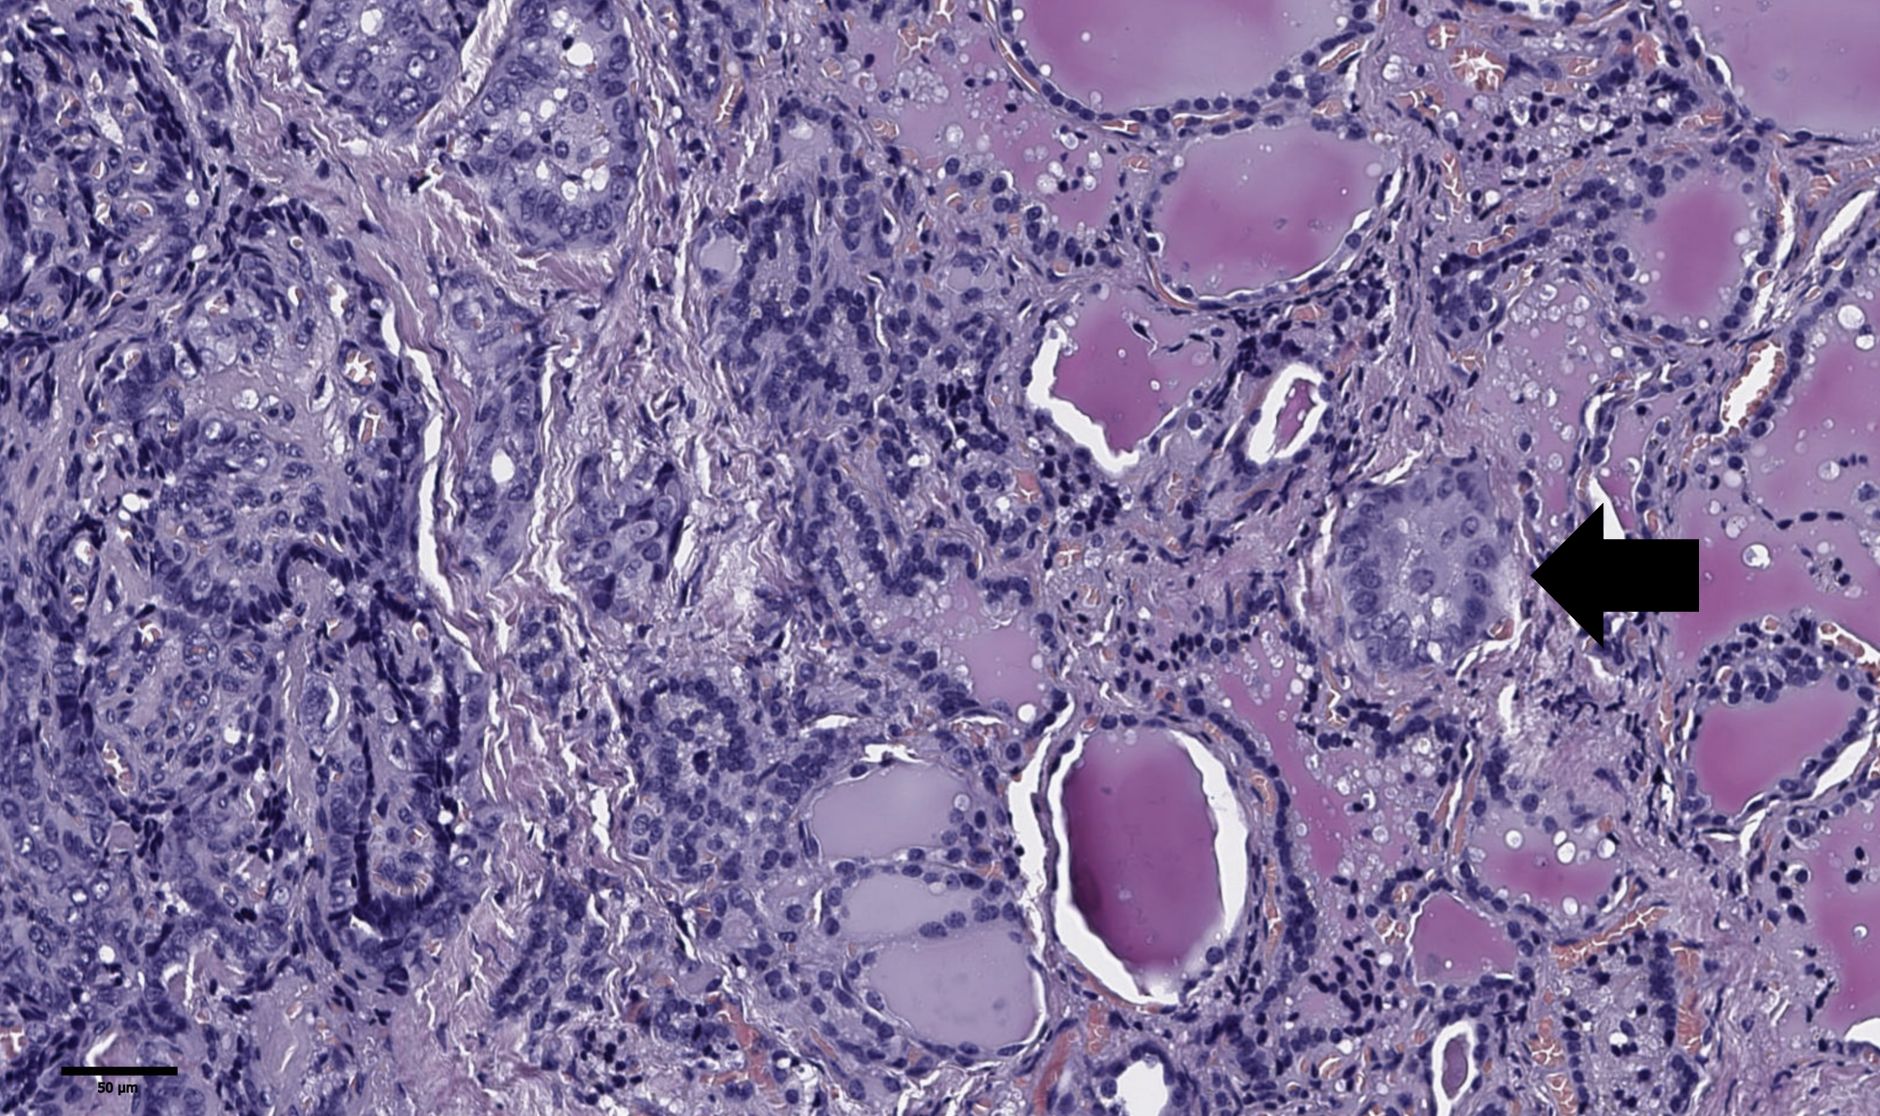

The groups were compared based on a number of tumor morphological features. The following were evaluated: the largest tumor node (Figure 1) and metastatic focus size (Figure 2), the histological subtype of papillary carcinoma according to the WHO classification (26), the presence of tall cell (Figure 3), Warthin-like, and squamous cell components in the tumor, foci of calcification and ossification in the tumor, a lymphocytic rim around the tumor node in the thyroid lobe tissue, apical vacuoles in tumor complexes, psammoma bodies in the tumor tissue (Figure 4) and in the thyroid tissue outside the tumor, the presence of a tumor capsule or its fragments, tumor “buds” (Figure 5), invasion of adipose tissue, perineural invasion, concomitant nodular thyroid diseases (tumor and non-tumor), and thyroiditis. Additionally, the following nuclear features of tumor cells were noted: angular contours, nuclear grooves, and intranuclear pseudoinclusions (Figure 6). Nucleoli in tumor cell nuclei were assessed using criteria partly adopted from the modified WHO/ISUP classification by S.A. Fuhrman for grading renal cell carcinomas (27), namely: the presence of nucleoli basophilic, visible but not prominent at ×100, or nucleoli conspicuous at ×100, basophilic, or nucleoli conspicuous at ×100, eosinophilic at ×400. Furthermore, the number of mitotic figures per 2 mm² of tumor tissue in “hot spots” and the presence of atypical mitotic figures were assessed. The degree of tumor fibrosis was visually graded as 0 (no fibrosis), 1 (fibrosis in less than 50% of the tumor node), or 2 (fibrosis in 50% or more of the tumor node) (Figure 7). A tumor “bud” was defined as a tumor complex no larger than 0.1 cm in diameter, located no more than 0.1 cm far from the tumor node, with one or more non-neoplastic thyroid follicles between them, which could not be reliably differentiated during routine histological examination between a tumor embolus in a vessel lumen (blood or lymphatic), an additional independent microfocus of tumor growth, or a tangential section of a tumor invasion area into adjacent thyroid tissue.

Figure 5. Histological images of tumor “bud” of papillary thyroid microcarcinoma (black arrow). A tumor “bud” was defined as a tumor complex no larger than 0.1 cm in diameter, located no more than 0.1 cm far from the tumor node. Hematoxylin–eosin, х100.

Thus, according to the univariate analysis of the overall patient group, an increased risk of synchronous regional lymph node metastases in unifocal papillary thyroid microcarcinoma was observed in patients with the classic tumor subtype, the presence of tumor “buds,” psammoma bodies in tumor tissue, and the absence of concomitant multinodular hyperplasia. Additionally, risk factors included a tumor node size ≥0.7 cm, BMI <22.9 kg/m², and age <52 years. However, in the multivariate analysis, only the presence of tumor “buds,” psammoma bodies in tumor tissue, and patient age showed significant associations with the risk of synchronous regional lymph node metastases. Therefore, in our definition tumor “buds” may indeed be a sign of more aggressive invasive tumor growth, intraorgan dissemination, or lymphatic vessel invasion. The possibility of de novo development of additional tumor foci cannot be entirely ruled out. Despite the identified morphological and clinical predictors of metastasis, the significance of these findings in the context of disease prognosis remains debatable, as overall and recurrence-free survival rates for papillary thyroid microcarcinoma remain extremely high (28, 29). In this study, we did not aim to determine the nature of tumor “buds” in each specific case. Further research using 3D visualization, immunohistochemical markers (e.g., CD31, D2-40), molecular profiling, and sequencing could clarify their nature—whether they are emboli, microfoci, tangential sections, or invasion areas. However, this process may be labor-intensive, costly, and not always successful due to the small size of such complexes (≤0.1 cm). Nevertheless, the term “tumor bud” seems appropriate as a risk factor detectable during routine histological examination. It should be noted that the term “tumor budding” is currently not used in the context of thyroid carcinomas. In histological evaluation of colorectal adenocarcinomas, it refers to single cells or small clusters composed of fewer than five cells located at the invasive front of the tumor (30). Therefore, the definition of tumor “budding” adopted in our study is novel and differs from the definition used in studies of colorectal carcinomas.